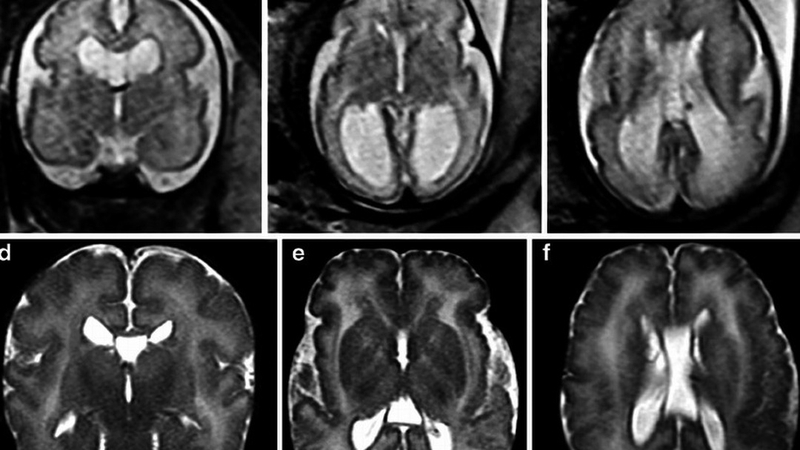

Hội chứng Zellweger hay còn gọi là hội chứng não gan, là một rối loạn di truyền hiếm gặp được đặc trưng bởi sự vắng mặt hoặc giảm chức năng của các peroxisome chức năng trong tế bào, ảnh hưởng đến quá trình oxy hóa beta của các chuỗi acid béo dài. Đây là một bệnh di truyền lặn trên các nhiễm sắc thể thường, gây ra nhiều vấn đề nghiêm trọng liên quan đến hệ thần kinh và các quá trình chuyển hóa trong cơ thể.